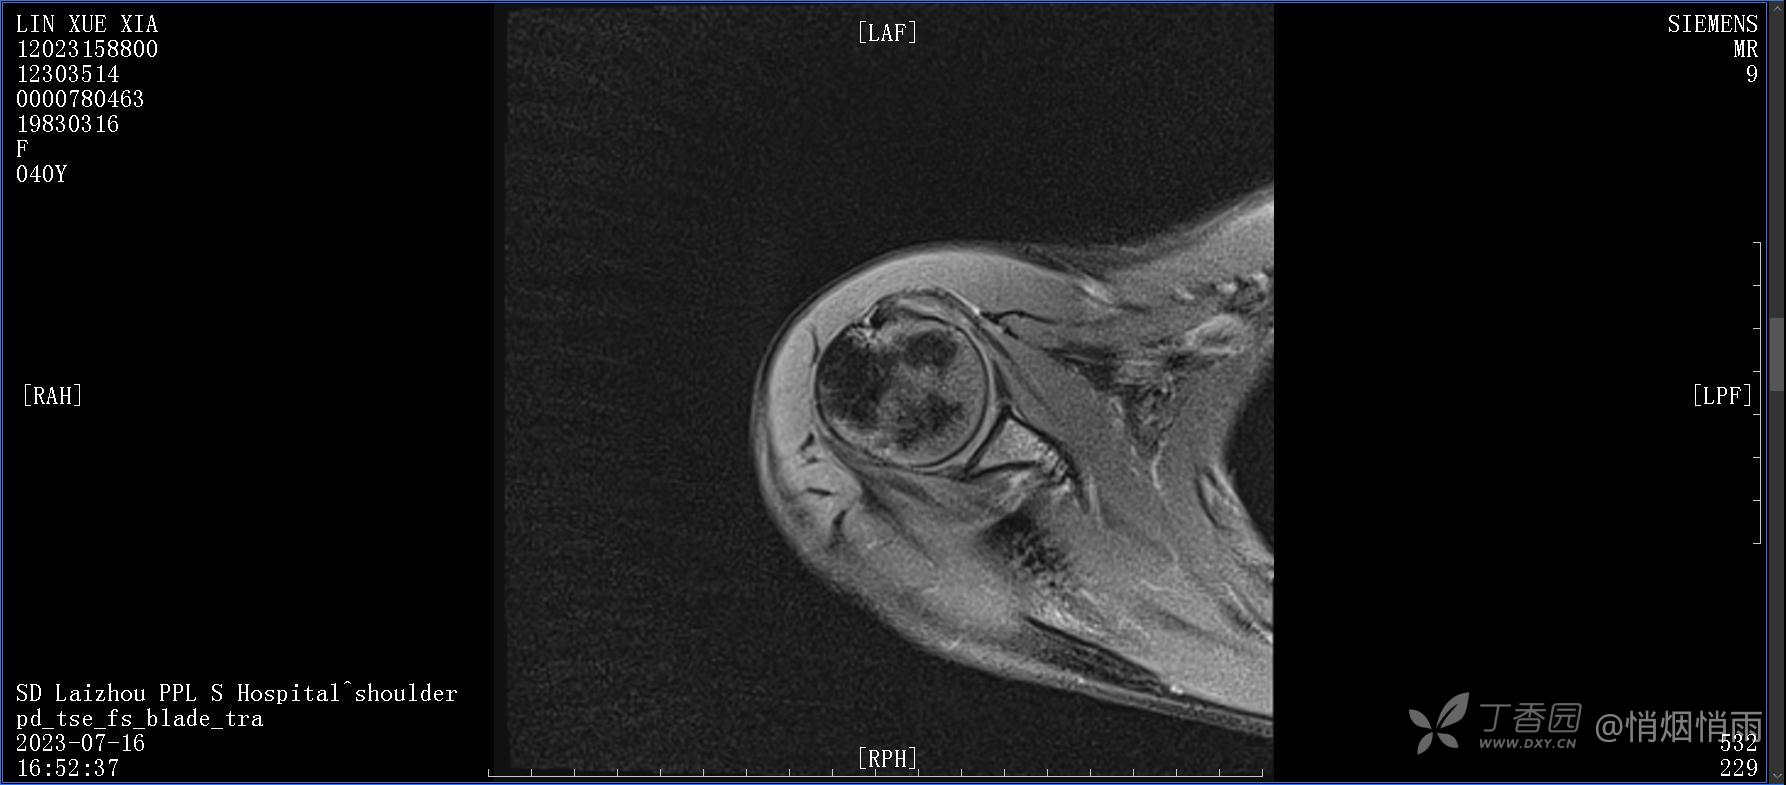

查体:右肩关节局部轻度肿胀,肩胛区压痛明显,痛处不固定,肩关节痛性活动受限,jobe test(+),lift -off test(+),中指、环指感觉较余指减退,余肢端感觉及血运情况可。

目前的诊断,暂时依据辅助检查诊为肩袖损伤,但是患者疼痛的性质和特点,却不是单纯的肩袖损伤所致。考虑过胸廓出口综合征,但是该疾病会出现肩胛区的疼痛吗?(由于考虑到费用的问题,没再进行下一步的检查)带状疱疹会有如此的症状吗?